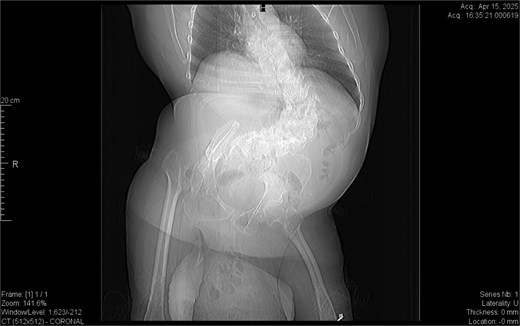

CT imaging (Figs 2–5) revealed a right inguinal hernia containing small bowel loops, ascending colon, the second and third portions of the duodenum, and the pancreatic head. The pancreatic head appeared rotated and displaced inferiorly into the hernia sac, without signs of acute pancreatitis.

Sagittal CT view inguinal hernial sac with pancreatic head and D2 and D3 segment of duodenum.